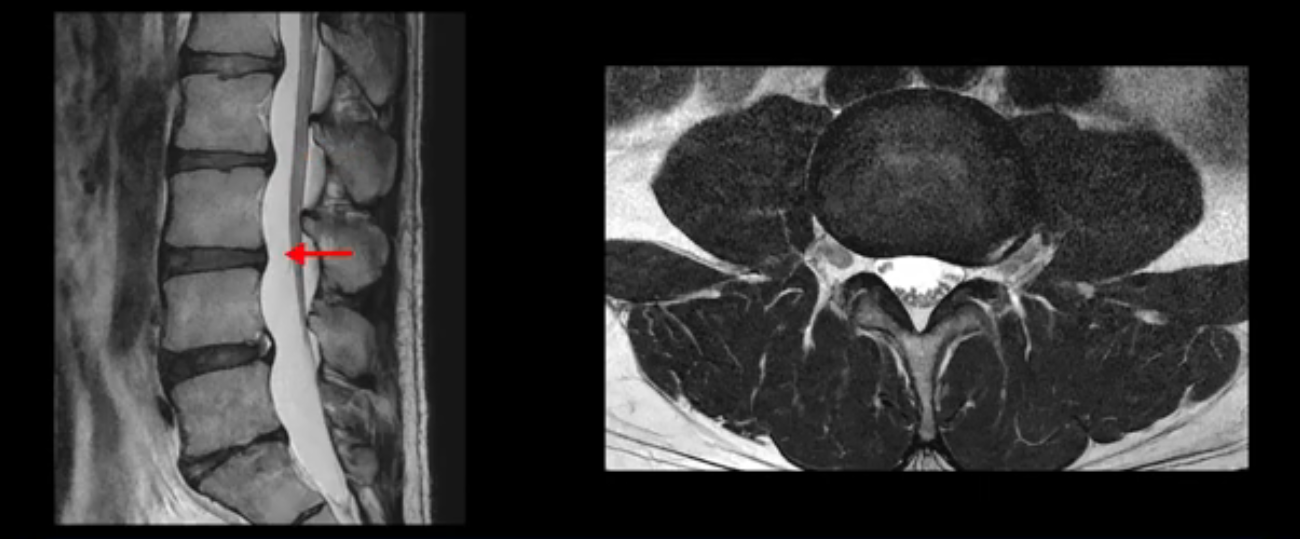

우선 이분 MRI를 보면 허리 모든 마디의 디스크가 퇴행되어 있고

여러 마디의 디스크가 조금씩 밀려나와 보이고, 디스크 섬유륜도 찢어져 보이는 마디도 보입니다.

그런데 이분의 증상과 MRI가 전혀 일치하지 않는데, 왜 그런지 지금부터 자세히 설명드립니다. 이분 증상은 앉으면 엉치와 허리가 심하게 아파 10분 이상 앉는 게 어렵고 양쪽 발가락이 앉아있을 때나 누워있을 때 다 저립니다. 걸을 때도 아파서 10분 걷기도 어렵습니다. MRI를 마디마디 살펴보면 1번 2번은 오른쪽으로 살짝 밀려나온 디스크가 있지만 전혀 심하지 않고, 뒤에 또 설명하겠지만 최근에 밀려나온 급성 디스크가 아니고 오래된 디스크로 판단됩니다.

2번 3번도 비교적 디스크 상태는 좋고 신경 구멍 넓이도 아주 넓습니다.

3번 4번도 마찬가지로 디스크상태 좋아 보이고 신경 눌림 전혀 없어 보입니다.

4번 5번은 가운데로 섬유륜이 찢어져서 디스크가 살짝 밀려나와 있지만 역시나 최근에 찢어지고 밀려나온 걸로 판단되지 않고 오래 전에 찢어진 흔적으로 보입니다.

왜 최근에 찢어진 급성이 아니고 오래된 거라고 하는지 이 부분도 뒤에 한꺼번에 설명 드리겠습니다.

5번 1번 역시 가운데로 디스크 조금 밀려 나와있지만 신경 공간 넓이는 아주 넓어서 신경 눌림 있을 거라고 예상이 안됩니다.

추간공도 보시다시피 왼쪽, 오른쪽 전부 다 매우 넓어서 신경이 눌릴만한 부분이 전혀 보이지 않습니다.